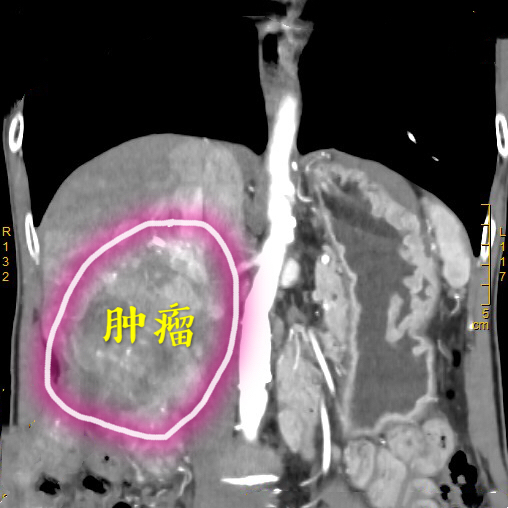

患者为65岁的老年男性,无意中发现右上腹有一个鸡蛋大小包块,偶尔会有胀痛,未予以重视,肿块进行性长大,检查提示肝脏肿物,遂到深大总院肝胆外科就诊。李晓武教授及其团队接诊后,发现患者较为消瘦,身高176cm却仅有43kg的体重,经查体发现患者包块巨大,下缘已达盆腔位置,极为罕见。进一步CT检查结果显示,患者的肿瘤已占据肝脏右叶大部分,直径达13cm,向后压迫下腔静脉,向下压迫结肠等肠管,并且伴有门静脉右支癌栓及右肝静脉癌栓形成。

李晓武 教授团队仔细阅读影像片后指出:肝脏恶性肿瘤手术既要保证肿瘤的根治切除,又需要保证手术切除后肝脏功能满足人体需要,手术、麻醉、术中出血、术后感染等对肝脏功能均有影响,此例患者肿瘤巨大,单是切除肿瘤已有很大难度;肿瘤与血管关系密切,术中出血也是个难题;切除后肝脏功能维持更是难点。需要术中精准切除、减少出血、尽量保留有功能肝脏及其功能血管,难度巨大。

经过周密的术前准备,2018年10月17日,肝胆外科李晓武教授团队给患者实施了精准右半肝切除术。术中探查结果与术前规划基本一致,整个手术历时2.5小时,术中釆用凝血器切肝,半肝血流阻断,切肝时间18分钟,切肝过程“0”出血,“0”输血,整个手术过程出血100ml。标本大小13*10cm,完美展现了精准肝切除、无血肝切除的理念。术后,患者生命体征平稳,清醒后送回普通病房。